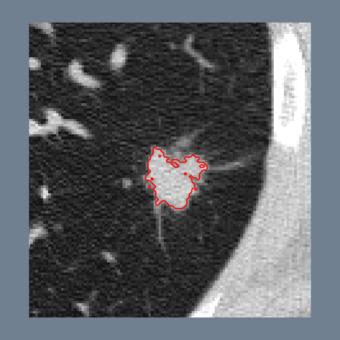

The Lesion Sizing Toolkit is an Open Source software package designed to segment and measure Lung Tumor Lesions from CT chest scans. This software is based on ITK, and it is intended to be contributed to ITK.